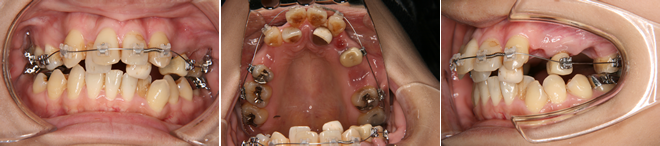

| 主訴 | 前歯が出ている |

| 年齢・性別 | 14歳 / 女性 |

| 治療方針 | 下顎の後退感が強い上顎前突。上顎片顎抜歯で対応。 |

| 抜歯部位 | 上顎左右小臼歯 |

| 使用装置 | パラタルアーチ、マルチブラケット装置 |

| 治療期間 | 23か月 |

| リテーナー | 上顎インビジブル、下顎スプリングリテーナー |

| 費用 | 825,000円(税別) |